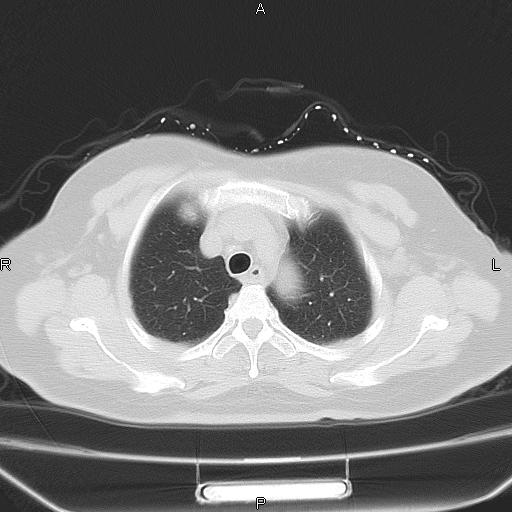

胸腺瘤

女、63Y 双眼睑下垂,早轻晚重。 胸腺瘤???

结果胸腺瘤